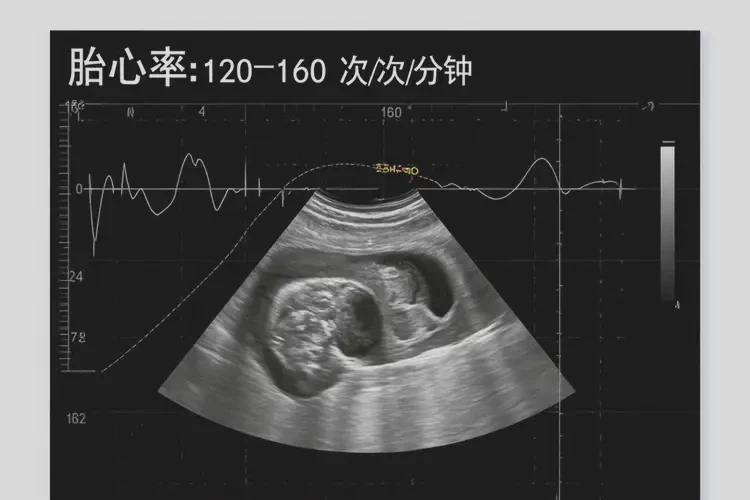

中期胎心率:在怀孕12-20周时,胎心率的正常范围是120-160次/分钟。此时,胎心率相对稳定,但仍需定期监测。

晚期胎心率:在怀孕20周以后,胎心率的正常范围仍然是120-160次/分钟。此时,胎心率的波动可能会减少,但仍需注意异常情况。